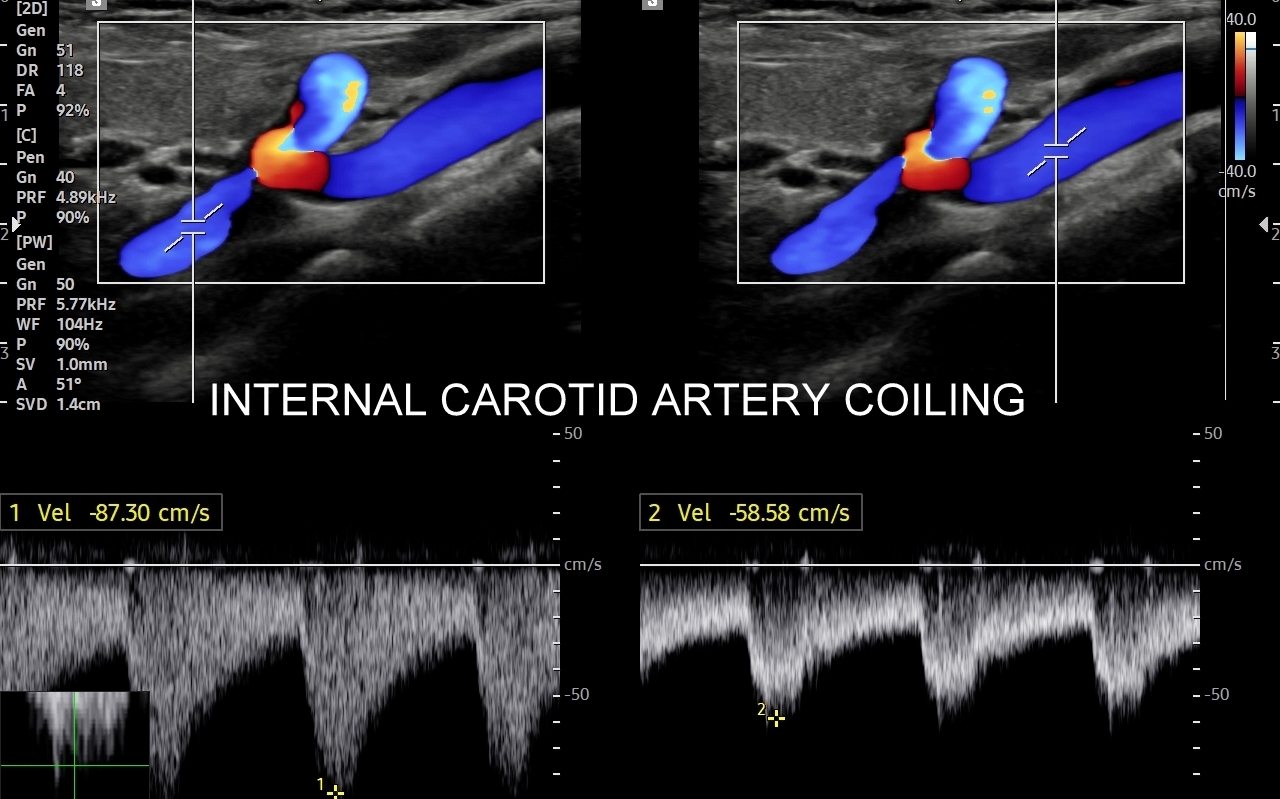

Badanie USG Doppler tętnic szyjnych i kręgowych, określane również jako badanie USG tętnic dogłowowych, to najczęściej wykonywane badanie diagnostyczne w układzie tętniczym. Wynika to z faktu, iż wymienione naczynia doprowadzają krew do jednego z najważniejszych organów człowieka, tj. mózgu, a choroby lokalizujące się w tętnicach dogłowowych mogą być źródłem różnorodnych objawów neurologicznych począwszy od zaburzeń pamięci i widzenia, poprzez bóle i zawroty głowy, aż do zgonu na tle nagłego udaru niedokrwiennego. W trakcie standardowego badania USG tętnic dogłowowych oceniane po obu stronach są tętnice szyjne wspólne, wewnętrzne, zewnętrzne oraz tętnice kręgowe. Badanie niejednokrotnie rozszerza się o specjalistyczną ocenę USG łuku aorty, USG tętnic podobojczykowych, USG tętnic skroniowych, czy o badanie USG Doppler przezczaszkowy.